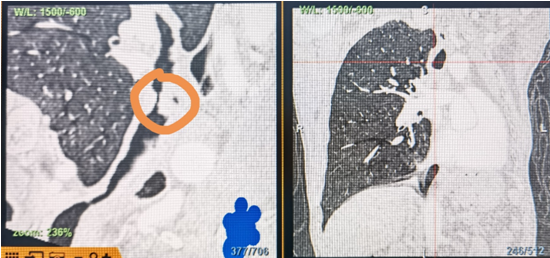

時間就是生命!了解患者病情后,歐陽海峰立刻啟動氣道梗阻緊急救治通道,協(xié)調(diào)院前轉(zhuǎn)運,急診快速入院流程。凌晨患者入院胸部CT顯示,現(xiàn)存唯一的呼吸通道在右主支氣管處,狹窄處僅約3毫米,患者命懸一線!

運用呼吸介入技術(shù),軟硬鏡結(jié)合快速開通氣道,是患者目前唯一可行的治療方案,手術(shù)刻不容緩!但存在麻醉后氣道完全塌陷閉合、大出血、窒息等巨大風(fēng)險?;颊叽饲敖舆B轉(zhuǎn)診3家醫(yī)院,均建議保守支持治療或轉(zhuǎn)院。歐陽海峰詳細(xì)了解患者病史,全面評估影像檢查結(jié)果后,決定盡快進(jìn)行手術(shù),組織醫(yī)護(hù)團(tuán)隊對患者進(jìn)行持續(xù)密切監(jiān)測,充分保障其術(shù)前安全。